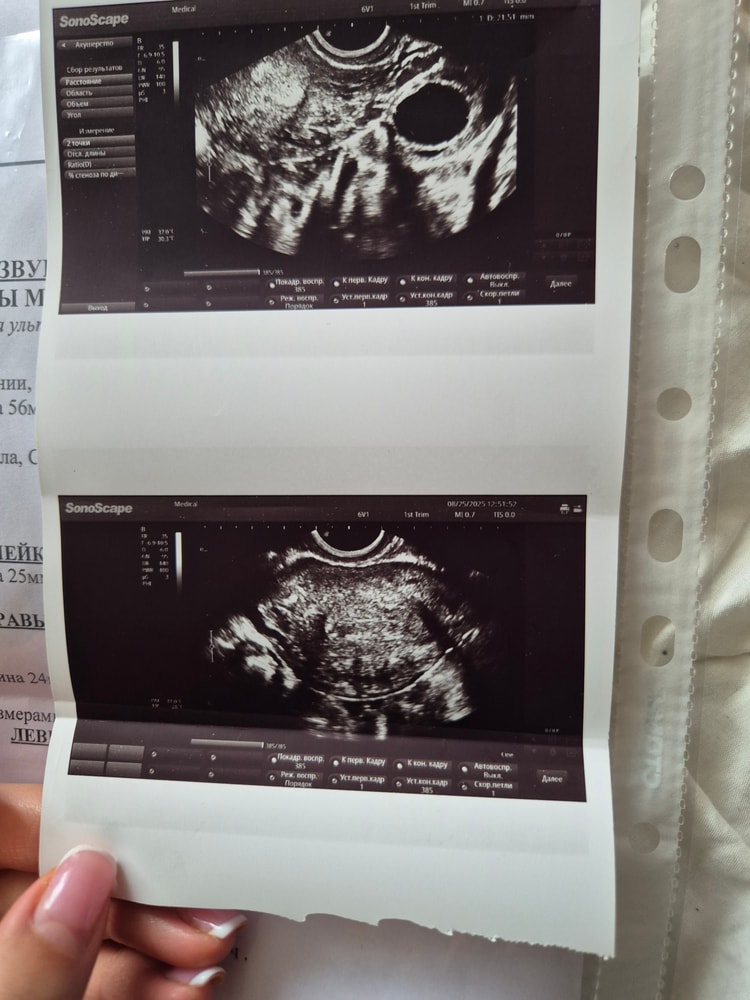

София , то есть сегодня 17й день цикла. Пишут на фото, что свободной жидкости нет, это значит овуляции не было ещё.

Abigeil, узи сделано сегодня Первый день кд 9 Августа

На данный момент беременность не реальна, тем более на 17 дц. На узи нет инфы за ЖТ даже

Делюсь счастьем 🥰 Желтое тело 10 дц